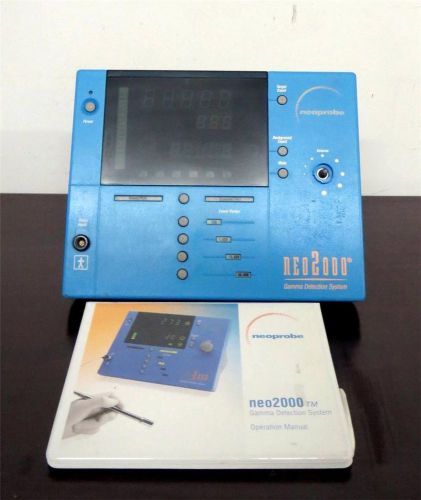

NeoProbe Neo2000 Model 2100 Gamma Detection System with User Manual